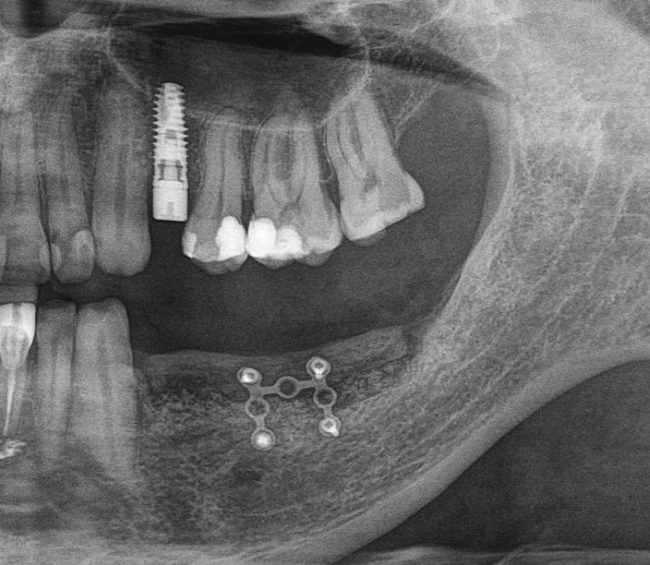

После операции мы делаем контрольные снимки. Это может быть ортопантомография:

или конусно-лучевая компьютерная томография. Как вам больше нравится.

Результат остеопластики методом остетотомии мы можем оценить уже через 4 месяца. Перед этим сделаем контрольные снимки (слева «до», справа «через 4 мес»):